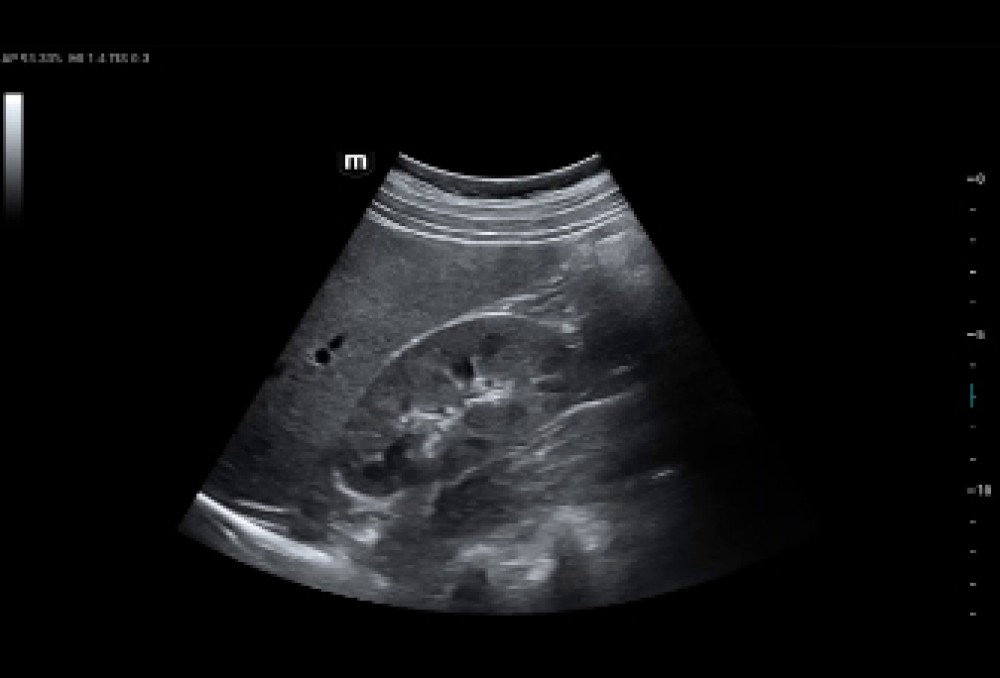

ZST+ Görüntüləmə Platforması: Zone Sonography Technology (ZST+) texnologiyasından istifadə edir; siqnal-səs nisbətini artırır və spekl artefaktları azaldaraq görüntü keyfiyyətini yaxşılaşdırır.